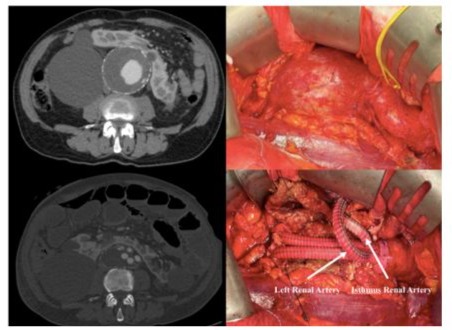

Figure 3: Retroperitoneal Approch

The study group consisted of 6 men and 1 female with a mean age of 69.6 (range 65-75). Preoperative patient’s risk factors and comorbidities were reported in Table 1. Mean aneurysm size was 6,2 cm (range 5,5-7,0 cm). Preoperative renal function was normal in all patients with a mean serum creatinine of 1,05 mg/ dl (range 0,8-1,3 mg/dl) and eGFR > 90 ml/min/1.73 m2 (range 88-94 ml/min/1.73 m2). In 6 (85 %) cases, a median laparotomy was performed and in 1 (14 %) case a retroperitoneal approach was preferred. Aorto-aortic graft interposition was performed in 5 cases (71 %), while in the remaining 2 (28 %) a bifurcated aortoiliac graft was executed. In one of the bifurcated grafts, a jump from the right prosthetic branch to right common femoral artery was necessary due to a preoperative occlusion of external iliac artery (Figure 4). The accessory renal arteries were replanted on the prosthesis in a single aortic patch in 6 (85 %) cases (Figure 2) and in 1 case, by the retroperitoneal approach, a bypass for the isthmus renal arteries and the principal left renal artery were performed (Figure 3). In 1 case we perfomed a longitudinal dissection of renal isthmus. Mean intensive care unit length of stay was 1.5 days (range 1-2 days) with a mean hospital length of stay of 5 days (range 4-8 days). In 6 (85 %) cases there was no change of renal functions, only in 1 (14%) patient the serum creatinine level reached 2 mg/dl post operatively with recovering creatinine levels after 7 days (Table 2).No AKI was reported. Neither 30days death nor major complications or major adverse cardiac events (MACE) were described. At mean follow-up of 24 months (range 18-27 months) no reinterventions were required, and renal function remained well preserved in all patients.